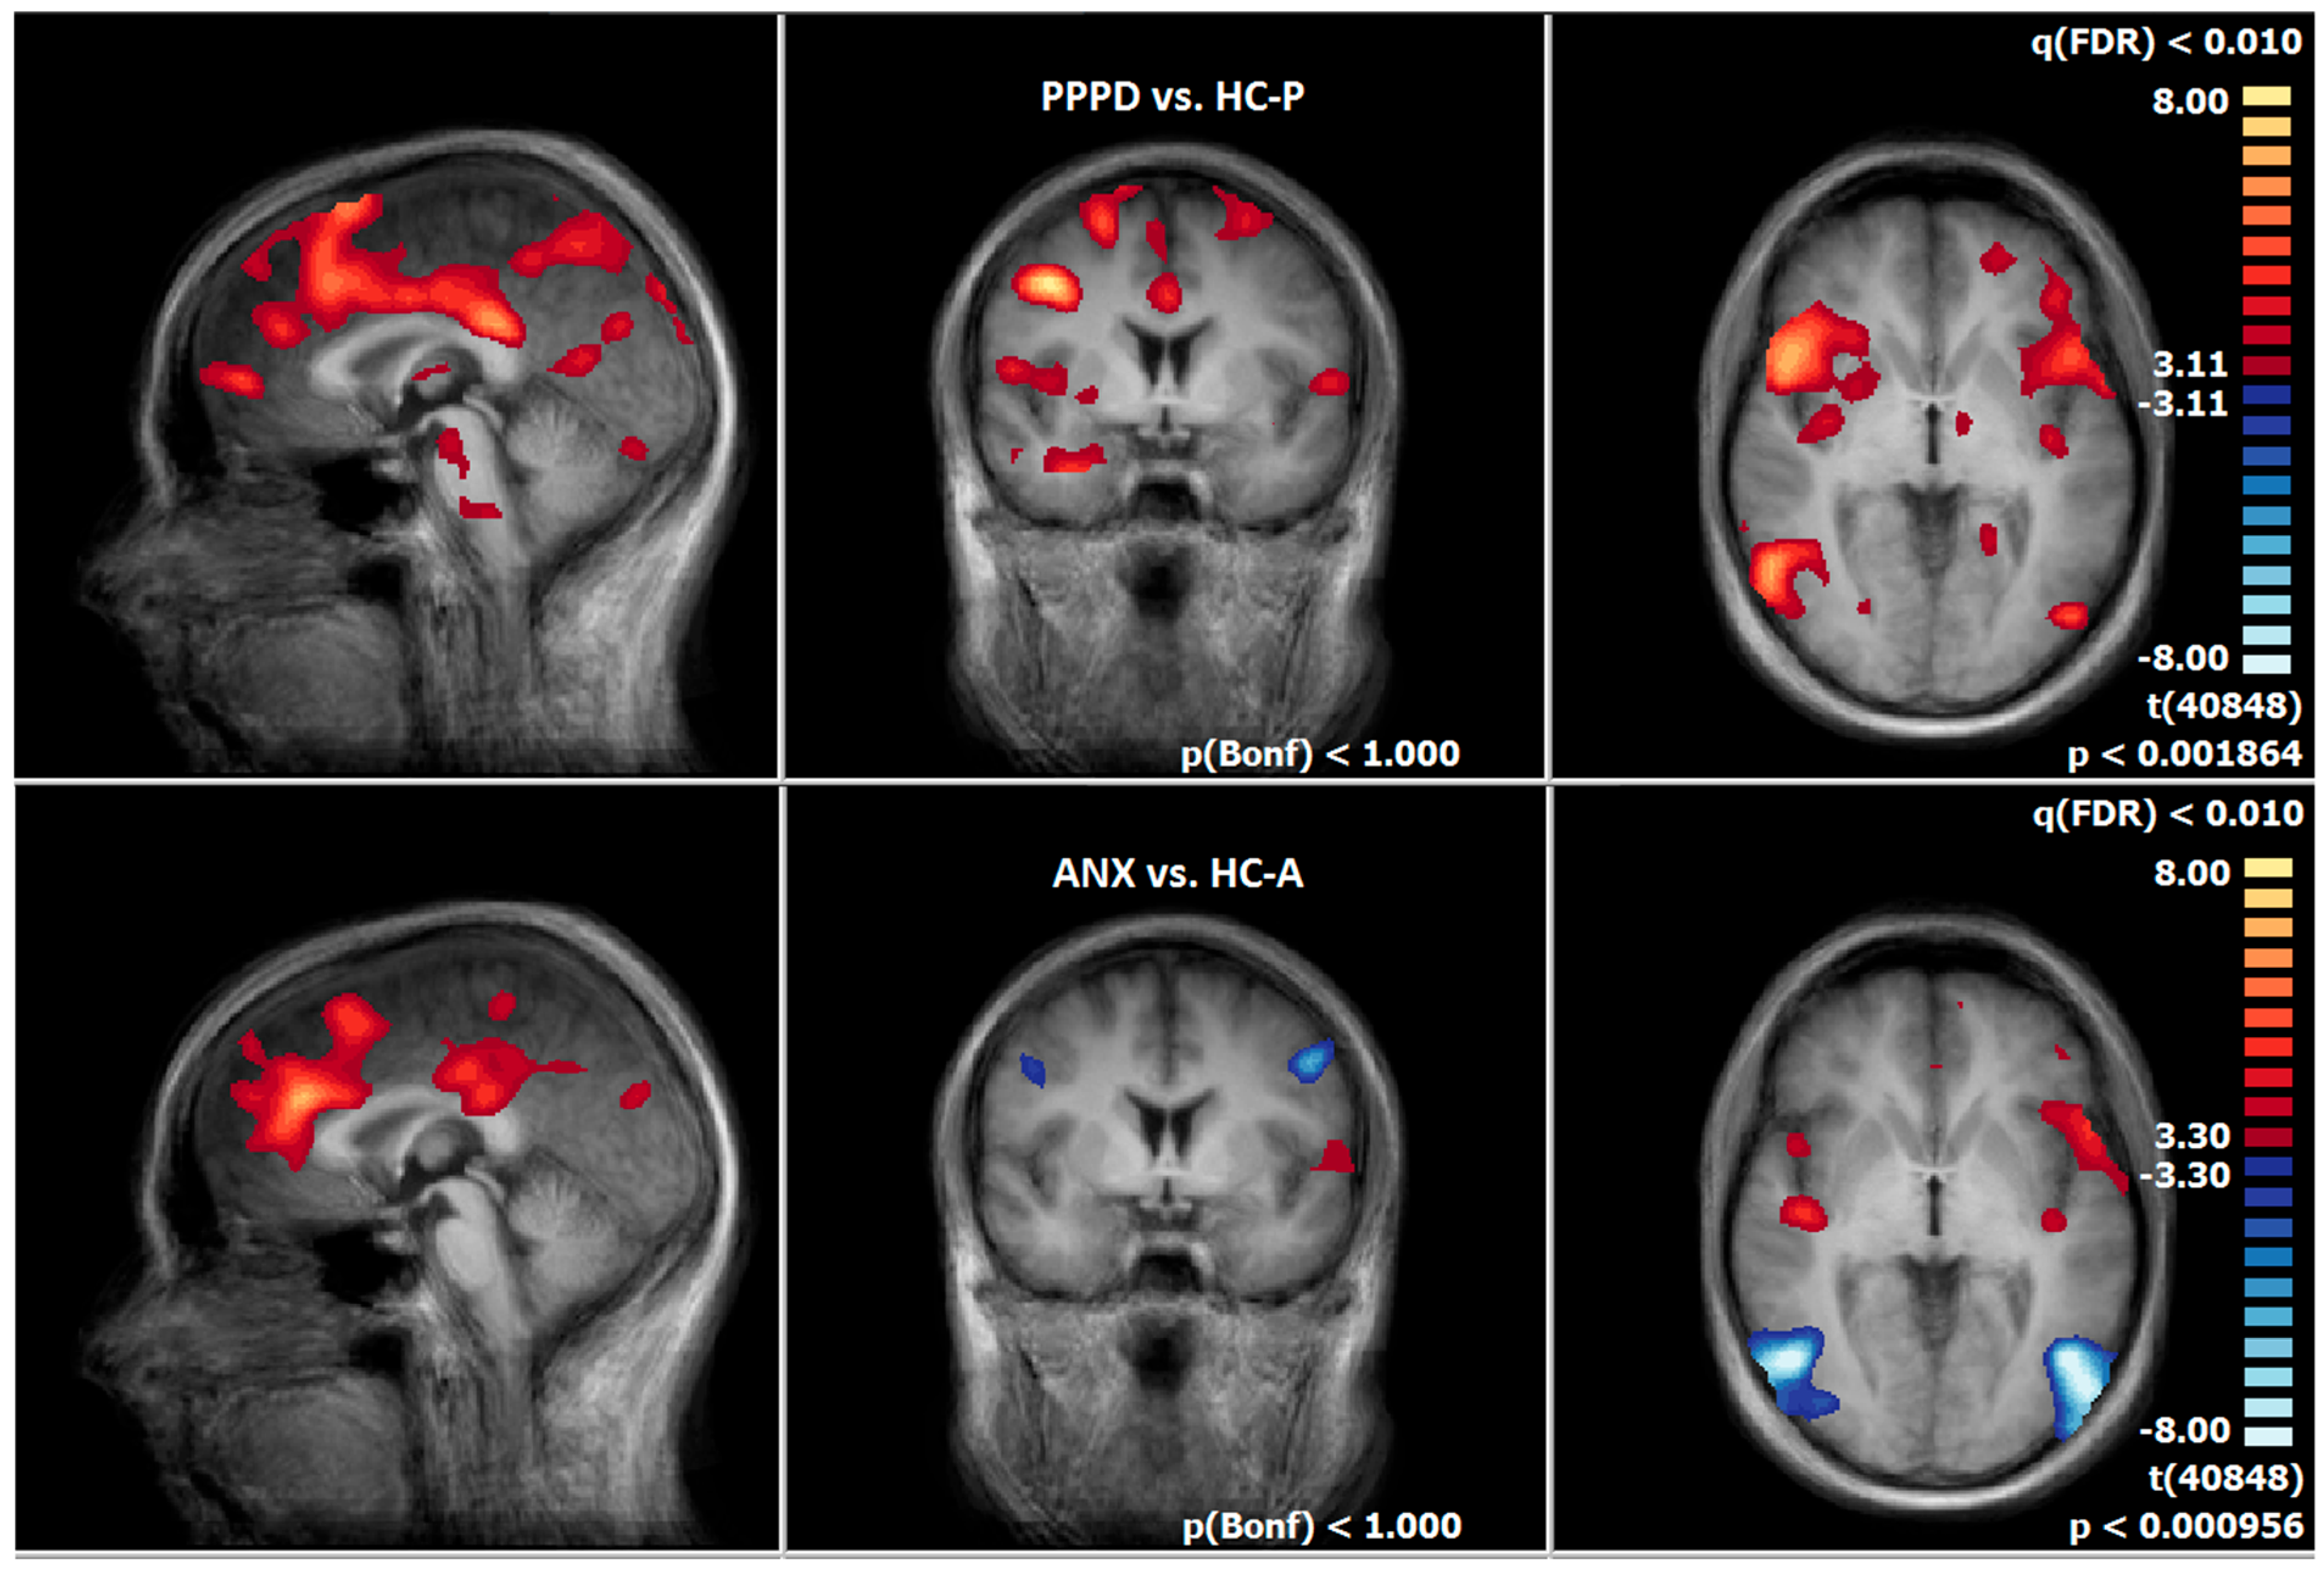

3.7. Post-Treatment Comparison of Neuronal Responses Between PPPD and ANX

3.8. Post-Treatment Comparison of Neuronal Responses Between PPPD and HC-P

3.9. Post-Treatment Comparison of Neuronal Responses Between ANX and HC-A